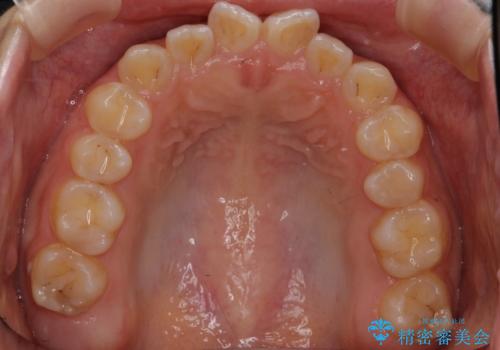

前歯のねじれ 乳歯を残して矯正治療

- 前歯のねじれを気にして来院。

左下に乳歯が残っていましたが、被せ物に穴が空いている状態でした。

乳歯は抜かずに保存的な治療を行いました。

上下の正中が1本分ずれていましたが、ちょうど1本分で目立たず、また、右下の歯が生まれつき少ないことを利用して、最小限の歯の移動にとどめました。

乳歯はまだぐらついたりしていない状態だったため、しっかり虫歯を取り、根の治療も行いました。